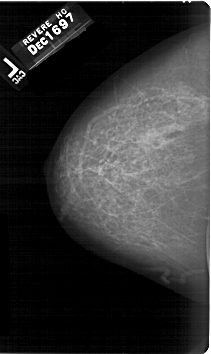

A_1402_1.LEFT_MLO

A_1402_1.RIGHT_MLO

A_1402_1.LEFT_CC

A_1402_1.RIGHT_CC

DATE_OF_STUDY 16 12 1997

PATIENT_AGE 59

DENSITY 3

LEFT_CC LINES 6721 PIXELS_PER_LINE 4006 BITS_PER_PIXEL 12 RESOLUTION 43.5 NON_OVERLAY

LEFT_MLO LINES 5866 PIXELS_PER_LINE 4456 BITS_PER_PIXEL 12 RESOLUTION 43.5 NON_OVERLAY

RIGHT_CC LINES 6856 PIXELS_PER_LINE 3961 BITS_PER_PIXEL 12 RESOLUTION 43.5 OVERLAY

RIGHT_MLO LINES 5791 PIXELS_PER_LINE 3976 BITS_PER_PIXEL 12 RESOLUTION 43.5 OVERLAY

LESION_TYPE MASS SHAPE LOBULATED MARGINS ILL_DEFINED

ASSESSMENT 4

SUBTLETY 4

PATHOLOGY MALIGNANT